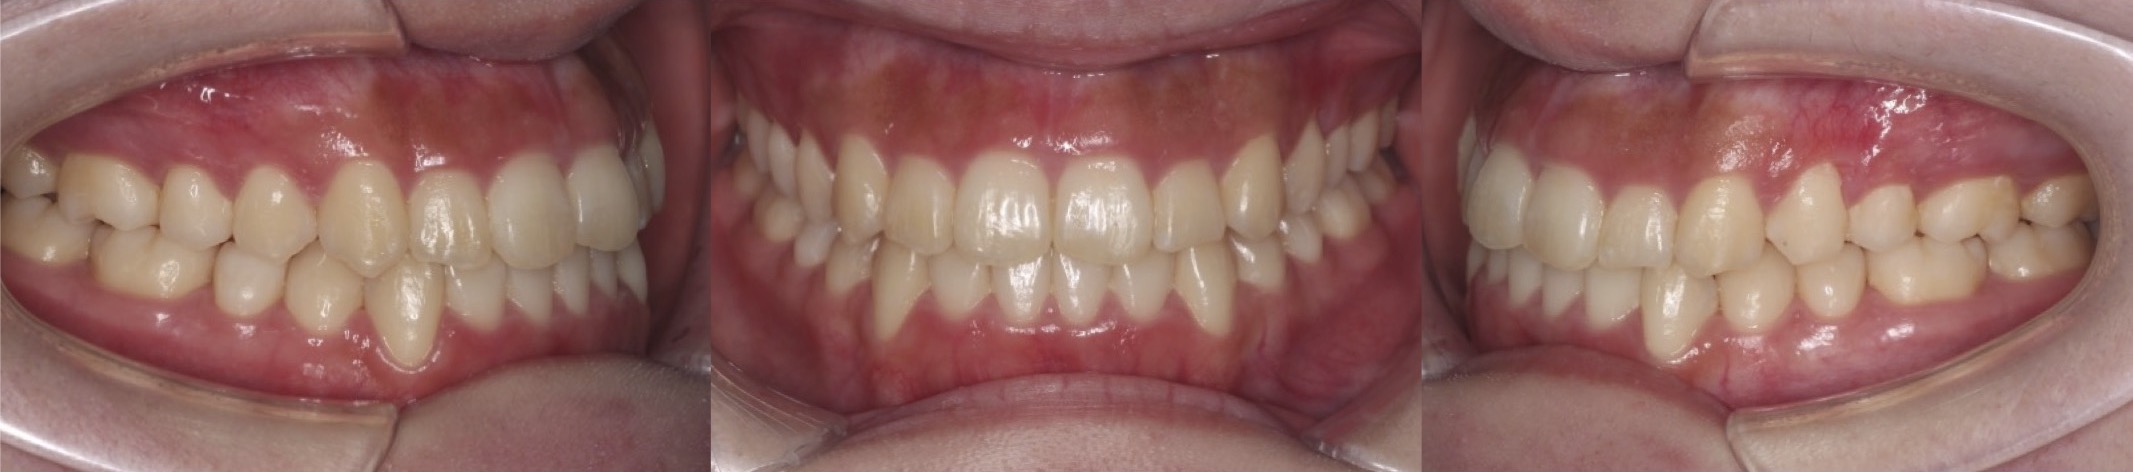

高校生女性・中程度叢生・マウスピース型装置

左側の片側のみに八重歯があり、上下の正中線が不一致となっている症例です。前歯のかみ合わせも上下がしっかりと当たるようになり健康な歯並びになりました。

<症例概要> 難易度★★★☆☆

主訴:八重歯

年齢・性別:高校生女性

住まい:千葉八千代市

症状:叢生・正中線の不一致

治療方針:上顎後方移動・IPR

治療装置:マウスピース型矯正装置(アライナー装置)

治療期間:1年7か月

アライナー枚数:49+16+15ステージ

リテーナー:上下+クリアタイプ

治療費用:990,000(税込)

代表的副作用:痛み・治療後の後戻り・歯根吸収・歯髄壊死・歯肉退縮

▶︎その他の副作用

【治療シミュレーション】

顎間ゴムを使用して、左上にスペースを作り八重歯を下ろしてきました。